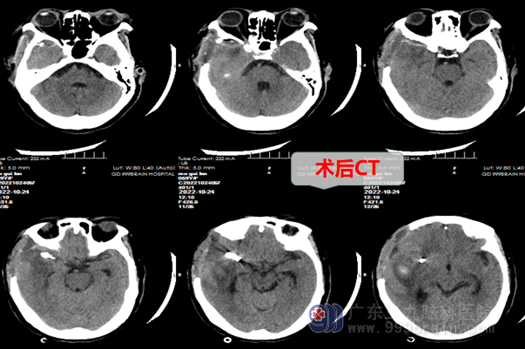

59岁的莫阿姨平时身子还算硬朗,洗衣做饭打扫卫生等简单家务活样样自己动手,从不用家人帮忙,平时也极少感冒发热,所以也很少往医院跑。近日不知道怎么回事莫阿姨突然感觉剧烈头痛,脑袋就像炸裂了一样,还伴有恶心呕吐,随后意识模糊昏迷了过去。家人一下子慌了手脚,急急忙忙将莫阿姨送到三九脑科医院神经外十科,经头颅CTA和MRA以及一系列检查发现,是由于右侧大脑中动脉动脉瘤破裂出血导致。在外十科欧阳辉教授详细询问病情得知,出血已有7个小时,随即外十科团队决定为莫阿姨走绿色通道进行急诊手术,向家属详细解释说明情况之后,紧急送入手术室。历经7个小时,手术医生、麻醉师、手术护士的积极配合下成功完成了动脉瘤颈夹毕手术+血肿清除术,考虑到其出血量大和术后短期内还有意识障碍,会出现呼吸困难,不得已为莫阿姨做了气管切开,保命要紧。莫阿姨术后经过一周精心的治疗和护理,现已能自动睁眼,意识正逐渐恢复,还需要慢慢进行一段康复治疗,未来康复指日可待。